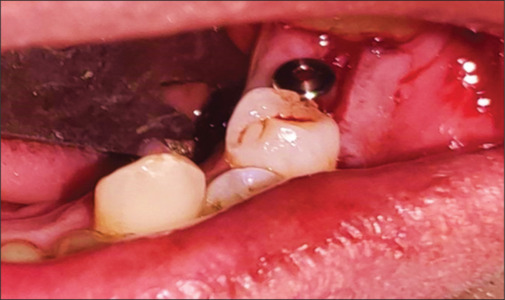

Background: To minimize the risk of impaired osseointegration historically, it has been recommended to insert the implant into the bone (submerged implants) and to allow for submerged healing of 3-6 months in the lower and upper jaw, this conventional technique is advocated. The concept of nonsubmerged healing was introduced in 1988 in which gingival former was placed at the time of implant placement instead of cover screw. The treatment concept of nonsubmerged implant placement enables early implant loading, one surgical procedure only, and a reduced treatment period for the patients.

Materials and method: A prospective split-mouth study of a minimum of 20 bilateral edentulous patients (total of 40 sites) was selected and randomly distributed in two groups: submerged and nonsubmerged implants. Patients were evaluated clinically and radiographically by assessing the patients on clinical parameters which included peri-implant probing depth, mucosal thickness, and width of keratinizing gingiva. Radiographic parameters were crestal bone height-distance between implant shoulder and alveolar crest compared from the bone level, on intraoral periapical.